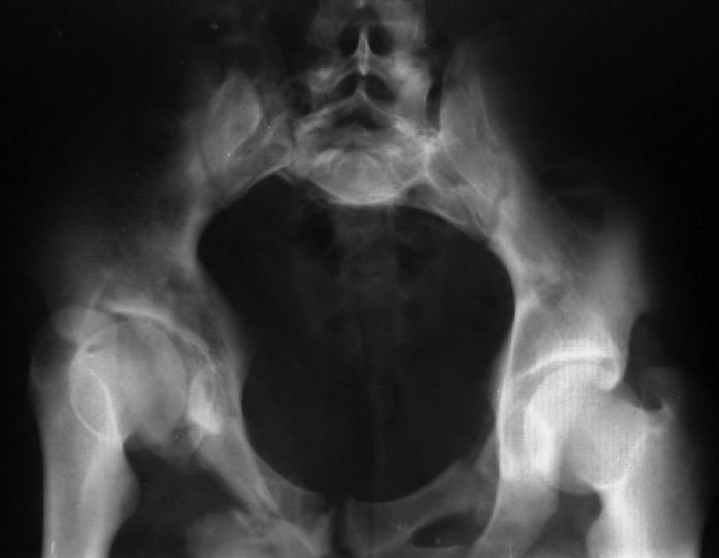

Уважаемый Юрий Алексеевич, обсудить показания к оперативному лечению возможно после выяснения полной клинической картины (боль, опороспособность, ходьба, сидение, половая функция, неврологический статус), данные кт и косых проекций.

Для информации к размышлению о возможности исправления имеющейся деформации предлагаю похожий случай.